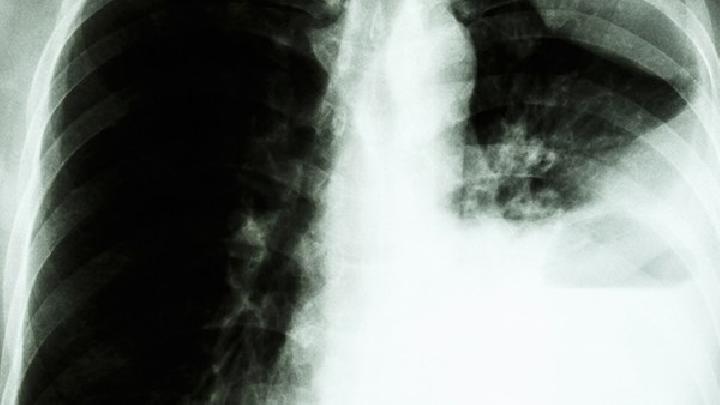

肺炎是我们日常生活中常见的疾病之一。肺炎在早期并不容易被观察到,所以它延迟了我们的最佳治疗时间。大多数人都害怕肺炎,尤其是一些孩子更容易患肺炎,接下来小边将介绍肺炎的症状,我希望你能仔细阅读!